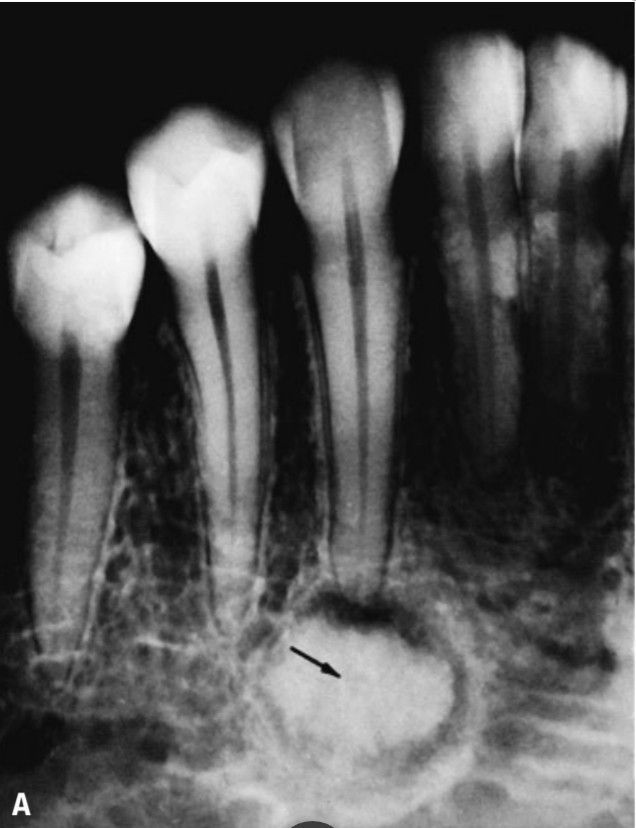

Periapical cementoma

“Cementoma” is a nonspecific term often used to describe localized masses of radiopaque condensed areas of the alveolus adjacent to the roots of the tee